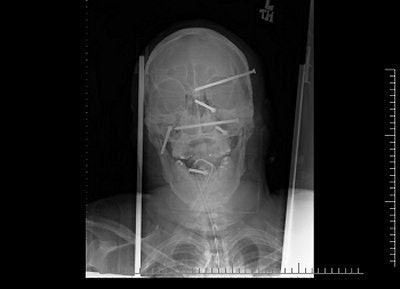

When the patient arrived at Providence Holy Cross Medical Center in Mission Hills, CA, it was clear he'd need more than an x-ray. But plain films were able to answer an immediate question: How many nails had been driven into his head?

Six nails, as it turned out, could be seen by anyone who saw the x-ray images released to the media earlier this year, after construction worker Isidro Mejia's impressive recovery from a horrific nail-gun accident.

"Nobody knew the extent of the injury until the first x-ray," said Dr. Rafael Quinonez, the neurosurgeon who operated on Mejia. "Nothing was sticking out."

"On physical exam you didn't see most of these," agreed staff radiologist Dr. Stephen Greenberg. "You'd see puncture wounds, you'd see blood, but you wouldn't really know exactly where the nails were."

Initial x-rays showed there were six 3.5-inch nails in Mejia's head, and that his jaw bones remained intact. He immediately underwent a CT scan, with initial images showing significant metal artifact, as expected (images A-B below).